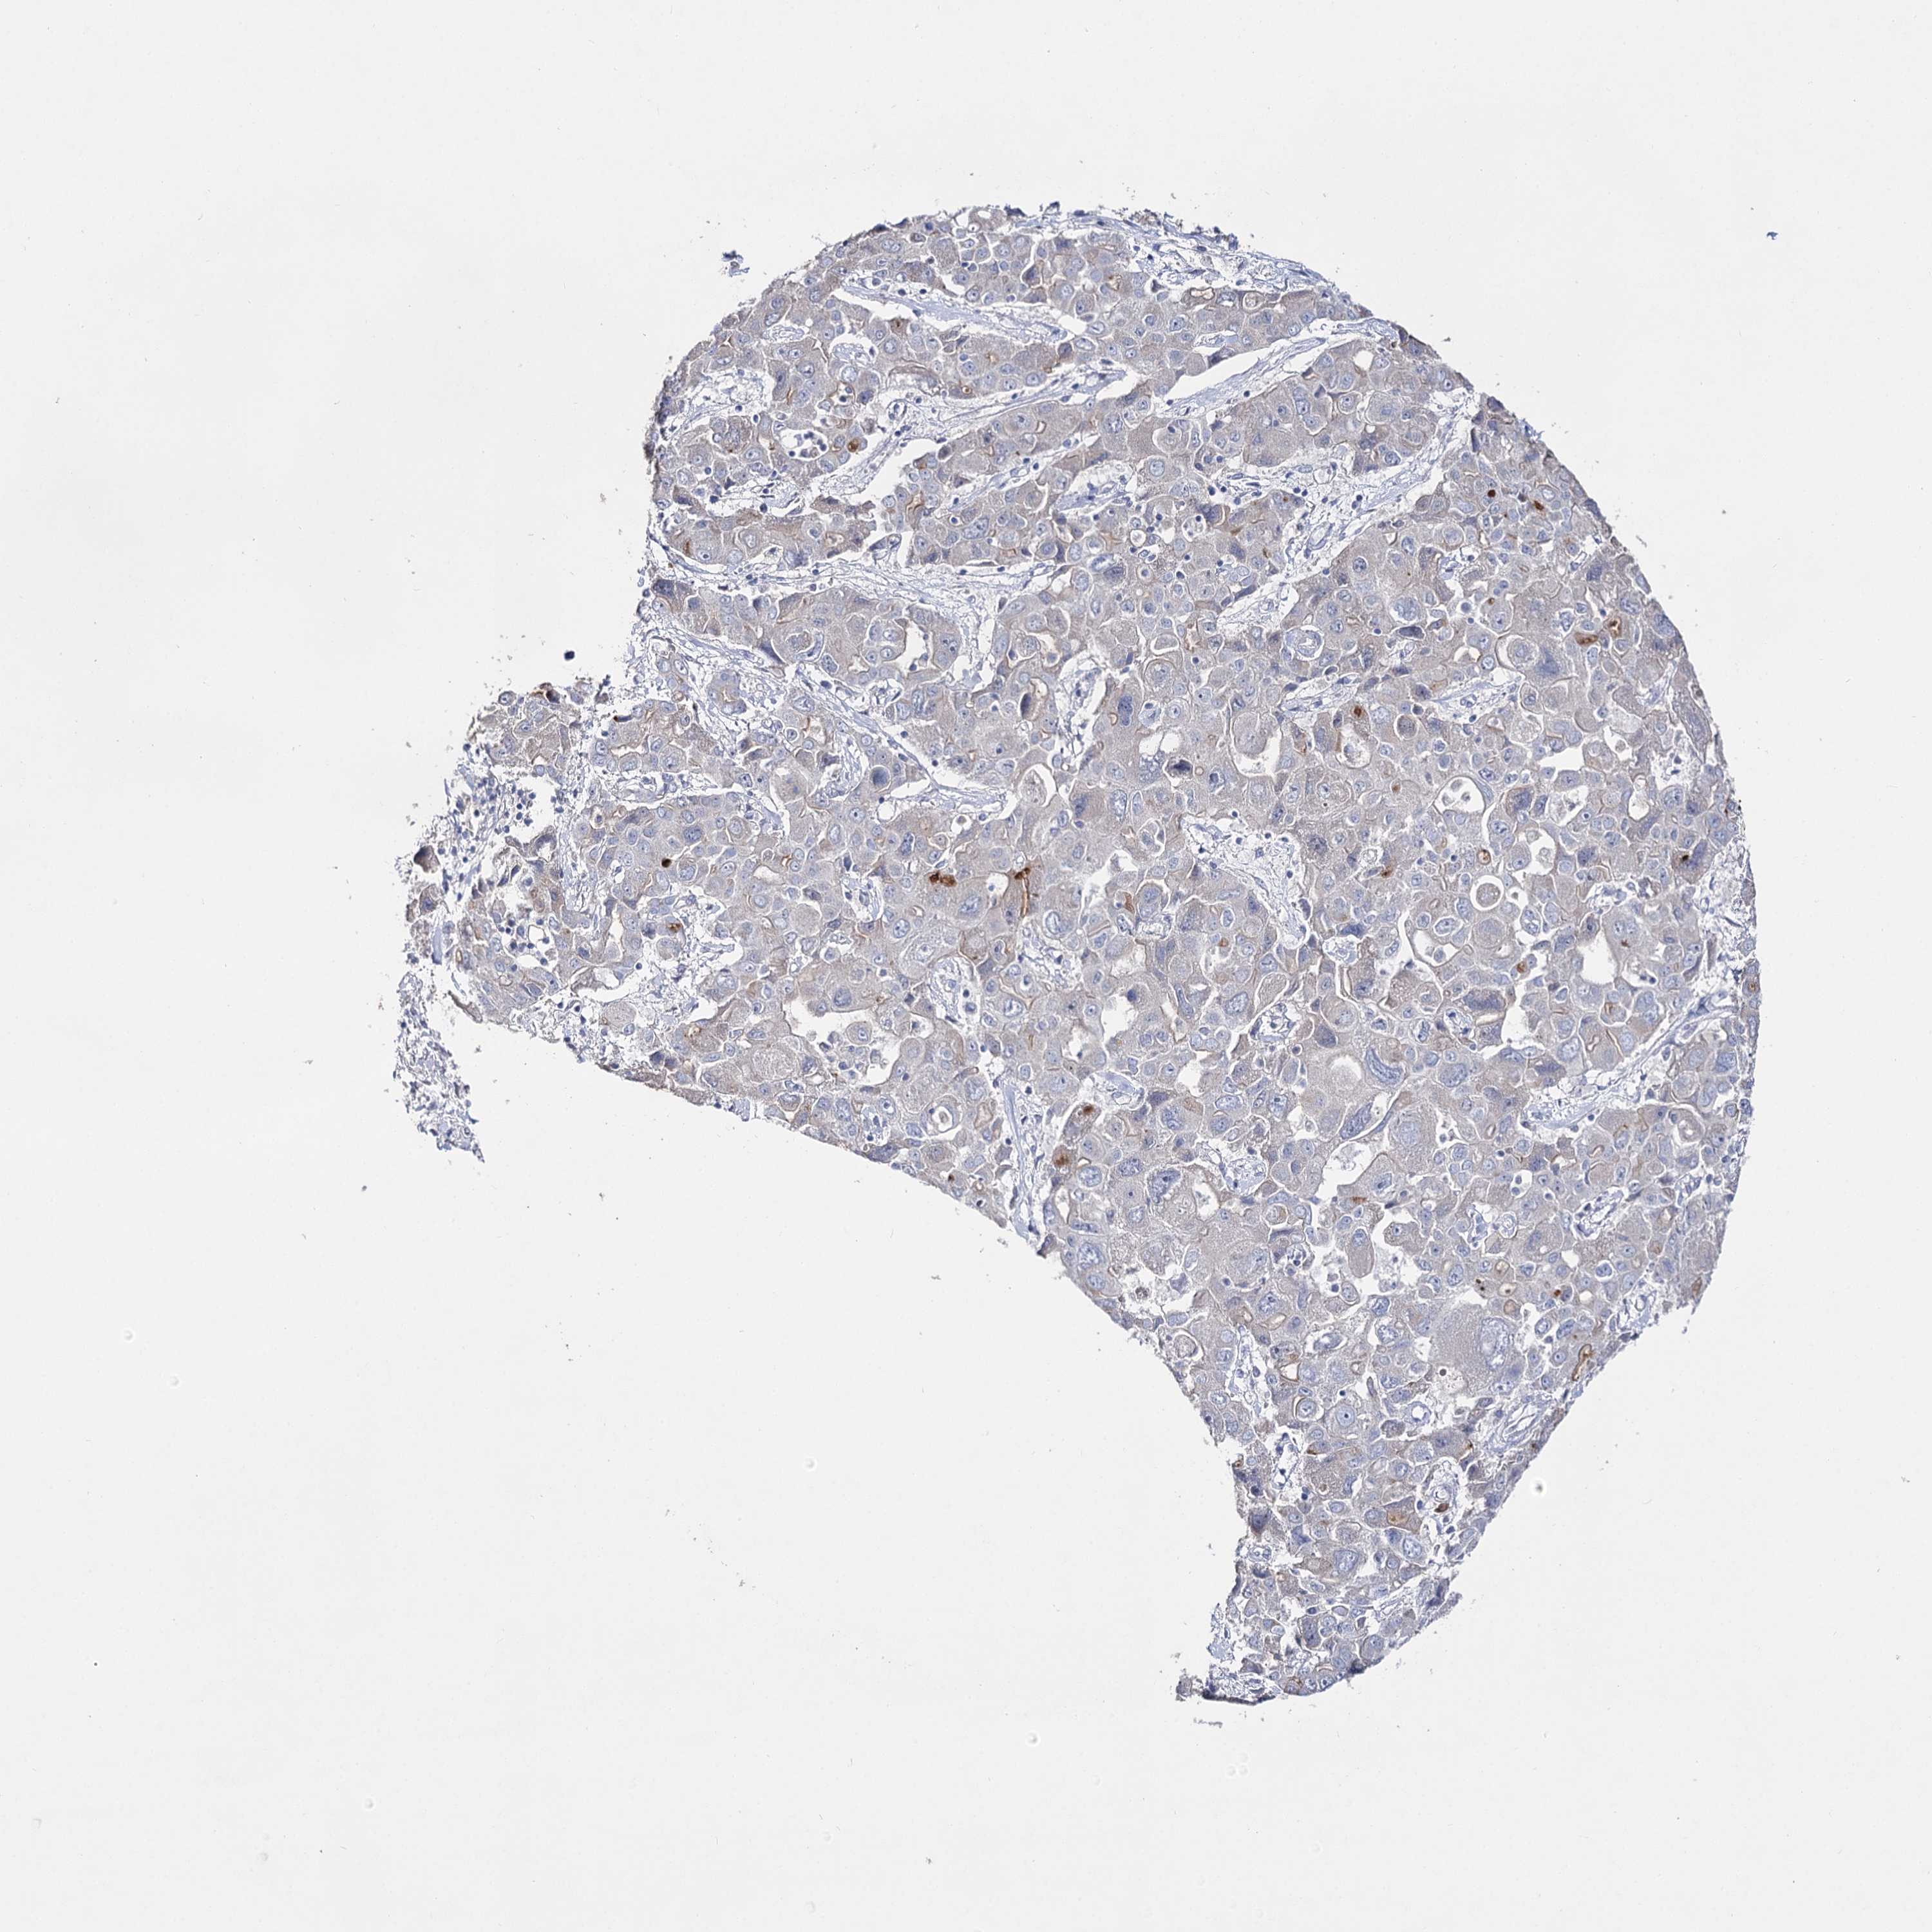

LIVER CANCER - Protein expressioni

A mouse-over function shows sample information and annotation data. Click on an image to view it in a full screen mode. Samples can be filtered based on level of antibody staining by selecting one or several of the following categories: high, medium, low and not detected. The assay and annotation is described here.

Note that samples used for immunohistochemistry by the Human Protein Atlas do not correspond to samples in the TCGA dataset.

Antibody stainingi

Antibody staining in the annotated cell types in the current human tissue is reported as not detected, low, medium, or high, based on conventional immunohistochemistry profiling in selected tissues. This score is based on the combination of the staining intensity and fraction of stained cells.

Each image is clickable and will lead to virtual microscopy that enables deeper exploration of all samples and also displays staining intensity scores, fraction scores and subcellular localization as well as patient and tissue information for each sample.

Antibody HPA037953

Antibody HPA037954

Staining

High

Medium

Low

Not detected

Intensity

Strong

Moderate

Weak

Negative

Quantity

>75%

75%-25%

<25%

None

Location

Nuclear

Cytoplasmic/membranous

Cytoplasmic/membranous,nuclear

Cholangiocarcinoma

Carcinoma, Hepatocellular, NOS